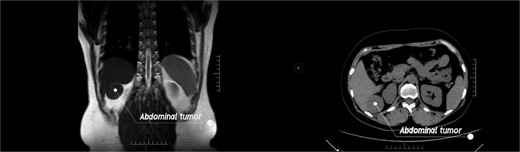

In this video (Video Clip 1), we report a case of a previously misdiagnosed patient with leiomyoma in the hepatorenal recess. A 44-year-old woman found a tumor between the liver and the kidney during a routine physical examination. Although the patient was asymptomatic, the doctor at the physical examination center recommended that patient come to our hospital for further consultation as the nature of the lesion could not be determined. Upon admission, the physical examination revealed no positive fings. The MRI examination identified a tumor in the hepatorenal space, suggestive of a benign tumor. The CT examination indicated an indistinct boundary between the tumor and the liver, suggesting its hepatic origin (Fig. 1). All other laboratory tests showed negative results. Plasma cortisol levels as well as renin and angiotensin were also within normal range. After fully communicating with the patient, it was decided to adopt a surgical treatment plan.